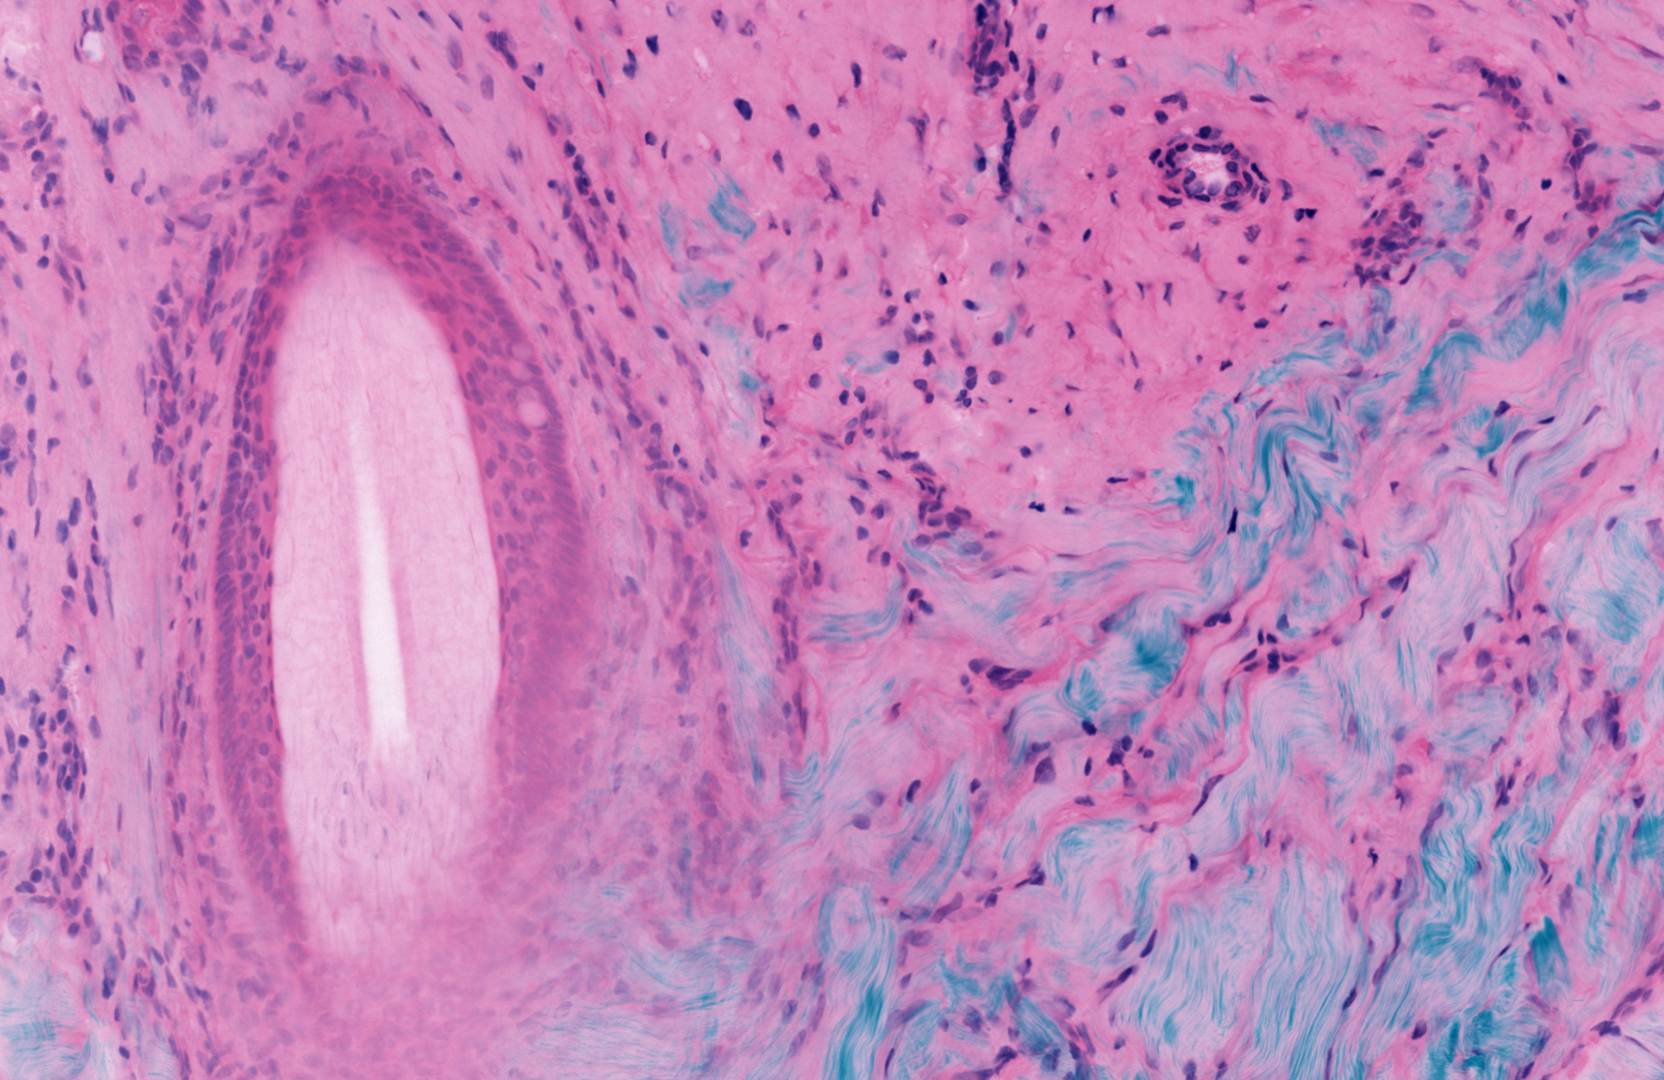

Magnification: Green is a fluorescent protein stain, red is a DNA stain, and blue is SHG in ordered Collagen tissue. DNA clusters in cell nuclei, proteins cluster in cell bodies, and collagen fibers form connective tissue in the skin sample. Image: Prof. Michael Giacomelli / University of Rochester